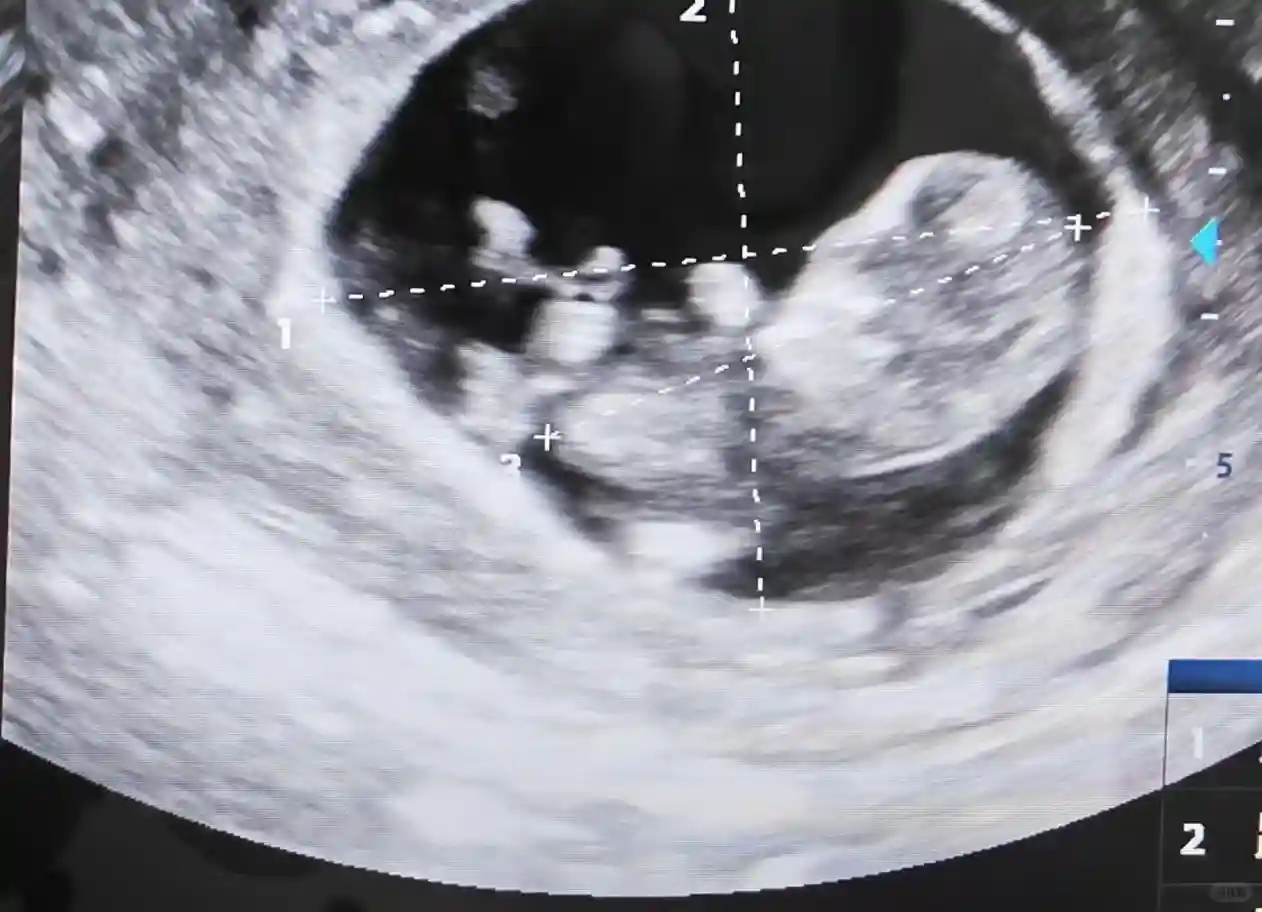

终于还是决定搏一搏做试管,看了好几个主任,最初想挂骆丽华主任,号太难挂,挂了骆主任团队的刘玮主任,第一次看诊,她不像有些主任问几句就让做检查,她看了我之前的检查,详细问了我之前的备孕过程,和我说了高龄试管的成功率,挺吓人的,但莫名让我有种安心的感觉。最终决定在她那做试管,之前她有告诉我一般我这个年龄,可能需要几次移植才能成功,让我做身体和心理准备。没想到一促一移上岸,哈哈。真的非常感谢她!

因为我的内膜也不太好,刘主任定了不鲜胚移植但胚胎好的方案促排(具体我也不懂),促排后又做了宫腔镜,过一个月后移植,竟然一次成功!现在已经8个月了,快到预产期啦。每次在省立做完产检,我都去刘主任那看看,安心我得感谢我的直觉选对了医生,感谢刘主任一路来专业仔细的陪伴,也感谢我自己选了就不多想,一步一步按照医生的要求做,希望后面一切顺利!